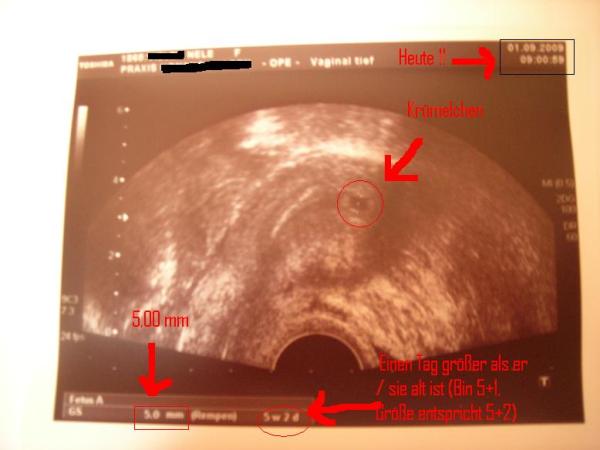

Hallo ihr lieben Hibbler! Wie ihr wisst gehör ich ja nun nicht mehr hier her und ich möchte euch einfach Mut machen, dass es gerade dann passiert, wenn mans nicht erwartet!!! 6 Zyklen voller Panikmache haben kein Ergebnis gebracht. War in ÜZ 7und hatte (wegen Zeitmangel und Stress) nur 3 (!!!) Mal GV! Das Ergebnis könnt ihr hier im Anhang sehen: Liebe Bald-Mamis, gebt die Hoffnung nicht auf! Liebe Grüße, nele

Bild zu Mut machen - Kinderwunsch - was tun, um schwanger zu werden?